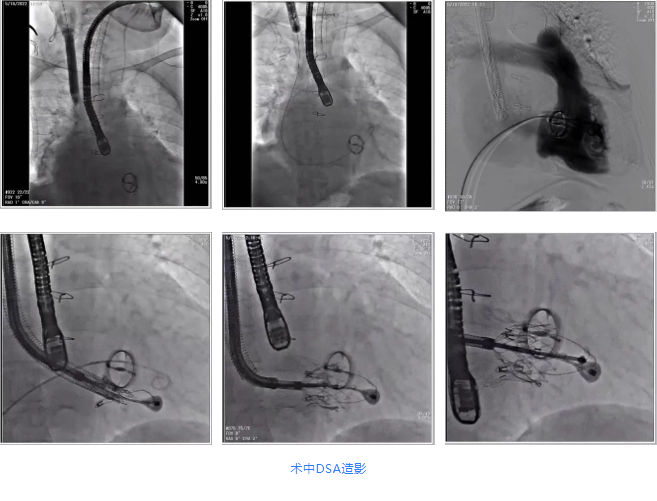

2022年5月18日,四川大學(xué)華西醫(yī)院心血管外科郭應(yīng)強教授團隊,在心內(nèi)科,麻醉手術(shù)中心,放射科,心臟超聲等各科室部門全力配合下,成功應(yīng)用LuX-Valve Plus為一例重度三尖瓣反流患者完成置換手術(shù)。團隊前期準備充足,通過術(shù)前評估,制定手術(shù)策略和預(yù)案。術(shù)后患者恢復(fù)良好,超聲顯示無反流和瓣周漏。此次手術(shù)是西部地區(qū)首例經(jīng)血管(頸靜脈)微創(chuàng)三尖瓣置換術(shù)(TTVR),也是華西醫(yī)院在探索經(jīng)血管三尖瓣置換領(lǐng)域新的開端,標志著西部地區(qū)結(jié)構(gòu)性心臟病診療邁向新的高度。

根據(jù)術(shù)前評估結(jié)果,郭應(yīng)強教授團隊為患者量身定制了手術(shù)策略,決定使用LuX-Valve Plus經(jīng)血管三尖瓣置換系統(tǒng)開展手術(shù)治療。手術(shù)在全麻下進行,采用經(jīng)右側(cè)頸靜脈入路,在經(jīng)食道超聲和DSA的指引下調(diào)整輸送器角度以達到正確位置,勾住前瓣后逐步釋放盤片,盤片打開后順利扎針,最終完成瓣膜植入,輸送器撤出。術(shù)后超聲提示人工三尖瓣同軸性良好,瓣架固定牢靠,無反流和瓣周漏,術(shù)后三尖瓣平均跨瓣壓差為1 mmHg。